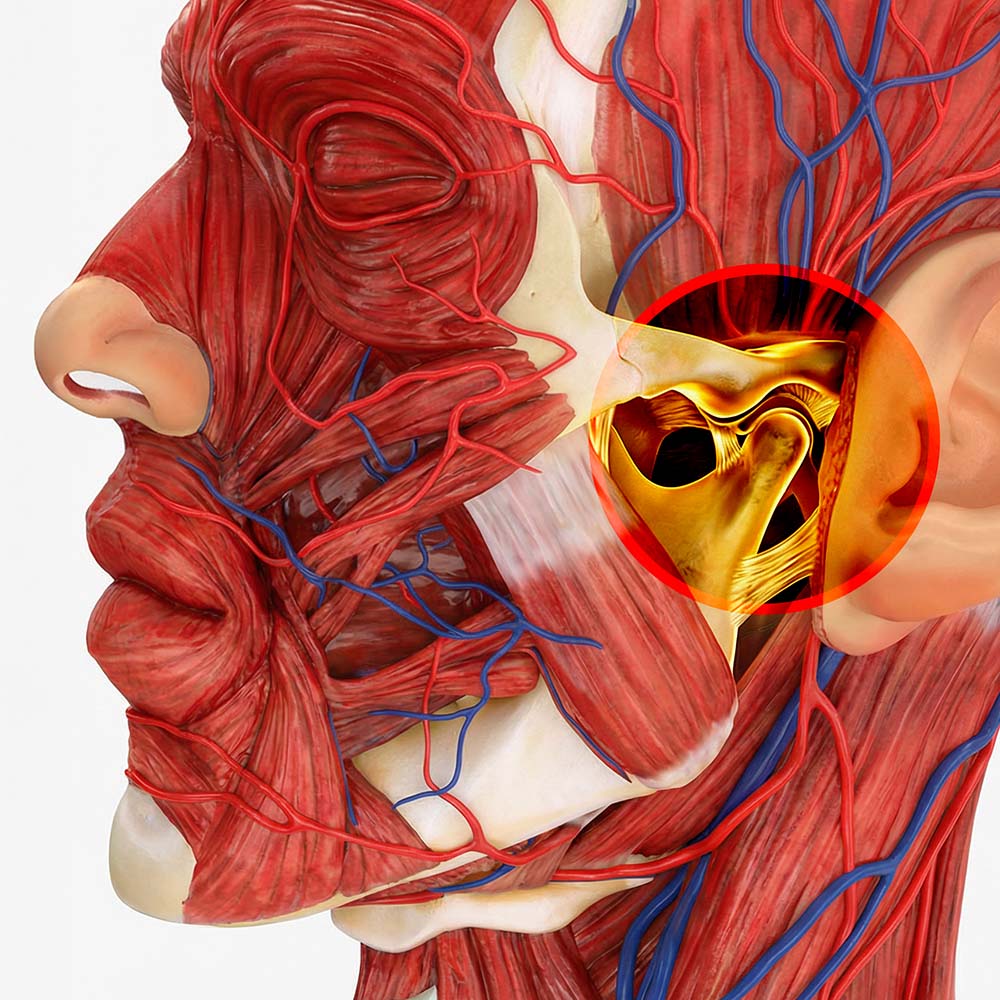

Articulação Temporomandibular

A Articulação Temporomandibular (ATM) é a estrutura que liga a mandíbula ao osso temporal do crânio, localizada logo à frente de cada ouvido. É considerada uma das articulações mais complexas do corpo humano, pois permite movimentos de dobradiça (abertura e fecho) e de deslizamento (para os lados e para a frente).